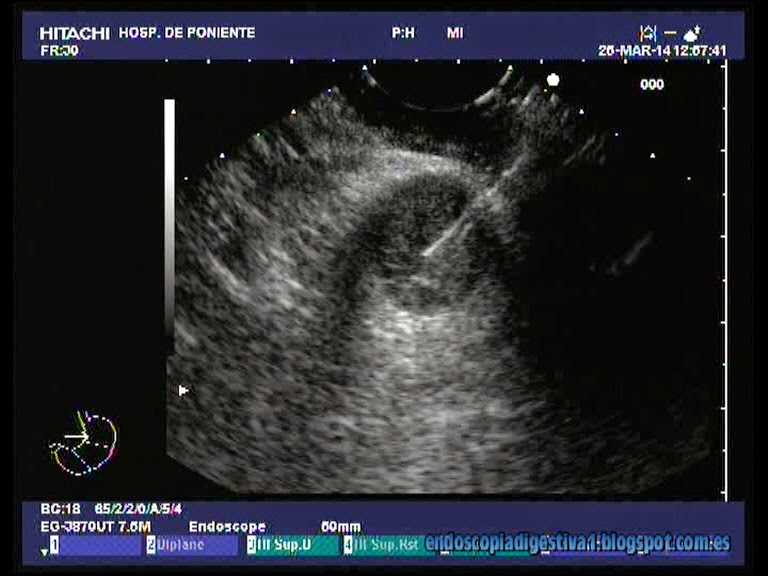

En seguimiento por neumología de nuestro centro por el cuadro respiratorio descrito. En los últimos 4 meses presenta una discreta afectación del estado general con dolor pleurítico en hemitorax izquierdo, encontrando en las pruebas de imagen (TAC torácico), múltiples bronquiectasias en el LSD (lóbulo superior derecho) e izquierdo (LSI). A nivel apical izquierdo hay una dudosa masa con pequeñas cavitaciones en su interior que sugieren mas una lesión residual postRT infectada que una neoplasia. También se aprecian múltiples adenopatías en el espacio subcarinal y ventana aortopulmonar (algunas cercnas a los 2 cm). Ante esta situación, con el objeto de descartar una neoplasia pulmonar o recidiva del cáncer de mama (dudosa masa apical izquierda), a la paciente se le realizan múltiples pruebas (broncoscopia, varios TAC torácicos, dos PAAF por TAC de la masa apical izda, etc). En las TAC-PAAF no se observan estructuras neoplásicas (estroma fibroso e inflamatorio que engloba acinos atróficos, sin atipia, estrógenos-, TTF-1 y Q-19 +). Se comenta el caso con nuestra unidad con idea de puncionar alguna de las adenopatías vistas en el TAC. Se realiza la USE-PAAF con aguja de 19G en el espacio subcarinal de una adenopatía homogenea, hiperecogénica de unos 16 mm de diámetro mayor. El estudio histológico descarta la presencia de celularidad neoplásica (compatible con lifadentitis reactiva). De esta forma, razonablemente se descarta un cuadro neoplásico pulmonar primario vs recidiva metastásica pulmonar y ganglionar de cáncer de mama.

La ecoendoscopia es una herramienta de gran utilidad en el estudio del mediastino, fundamentalmente en el estadiaje TNM del cáncer de esófago, pulmonar y metástasis linfáticas de estos tumores así como de otras localizaciones. En el estudio de las adenopatías, los espacios donde se suelen asentar y que tienen una gran importancia clínica son el espacio subcarinal y la ventana aortopulmonar. En este caso se ha realizado una punción con aguja del 19G a una adenopatía de 16 mm en el espacio subcarinal con éxito que permitió descartar un origen neoplásico de las lesione sencontradas en las pruebas de imagen radiológicas.